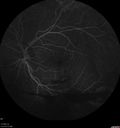

50 year old man: The patient noticed a few days ago, when putting on Contact Lenses for work which were slightly different from his usual strength. He therefore had some trouble at work with the new contact lenses. Then he had some haze in his vision. In the morning he went to see his mother in Venice and there was a new big black line in the left eye when he was getting up from lying down (this was yesterday). Then he noticed a lot of floaters in his vision that looked like blood. This has been fluctuating. You saw him this morning and asked him to come here. VA OD: Dcc20/20-2 NscJ1+ The patient has type I diabetes diagnosed at age 24 and he is now 50 years old VA OS: Dcc20/25+2 NscJ1+ IOP: TP: OD:17 OS:19

PDR and Vitreous Hemorrhage - High Risk Left Eye - Low Risk Right Eye412 views50 year old man with type I diabetes mellitus for 26 years. New Vitreous Hemorrhage in the left eye. Both eyes have NVE. Both also have foveal hypoplasia00000